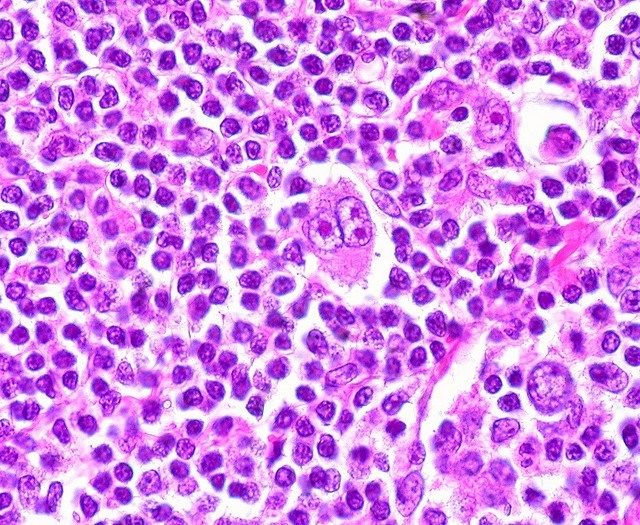

El linfoma difuso de células B grandes es el tipo más común de linfoma no Hodgkin. Debido a que es altamente variable biológicamente hablando, los pacientes responder de formas muy diversas al tratamiento. El ADN circulante del tumor se libera en la sangre al morir las células cancerosas. Aprender a elegir y leer estas secuencias de ADN entre los miles o incluso millones de otras secuencias no cancerosas en la sangre puede proporcionar "información valiosa" sobre el curso de la enfermedad y la efectividad de la terapia.